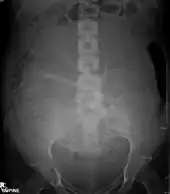

Projectional radiographs

Projectional radiography is the practice of producing two-dimensional images using X-ray radiation. Bones contain a high concentration of calcium, which, due to its relatively high atomic number, absorbs X-rays efficiently. This reduces the amount of X-rays reaching the detector in the shadow of the bones, making them clearly visible on the radiograph. The lungs and trapped gas also show up clearly because of lower absorption compared to tissue, while differences between tissue types are harder to see.[101]

Projectional radiographs are useful in the detection of pathology of the skeletal system as well as for detecting some disease processes in soft tissue. Some notable examples are the very common chest X-ray, which can be used to identify lung diseases such as pneumonia, lung cancer, or pulmonary edema, and the abdominal x-ray, which can detect bowel (or intestinal) obstruction, free air (from visceral perforations), and free fluid (in ascites). X-rays may also be used to detect pathology such as gallstones (which are rarely radiopaque) or kidney stones which are often (but not always) visible. Traditional plain X-rays are less useful in the imaging of soft tissues such as the brain or muscle. One area where projectional radiographs are used extensively is in evaluating how an orthopedic implant, such as a knee, hip or shoulder replacement, is situated in the body with respect to the surrounding bone. This can be assessed in two dimensions from plain radiographs, or it can be assessed in three dimensions if a technique called '2D to 3D registration' is used. This technique purportedly negates projection errors associated with evaluating implant position from plain radiographs.[102]